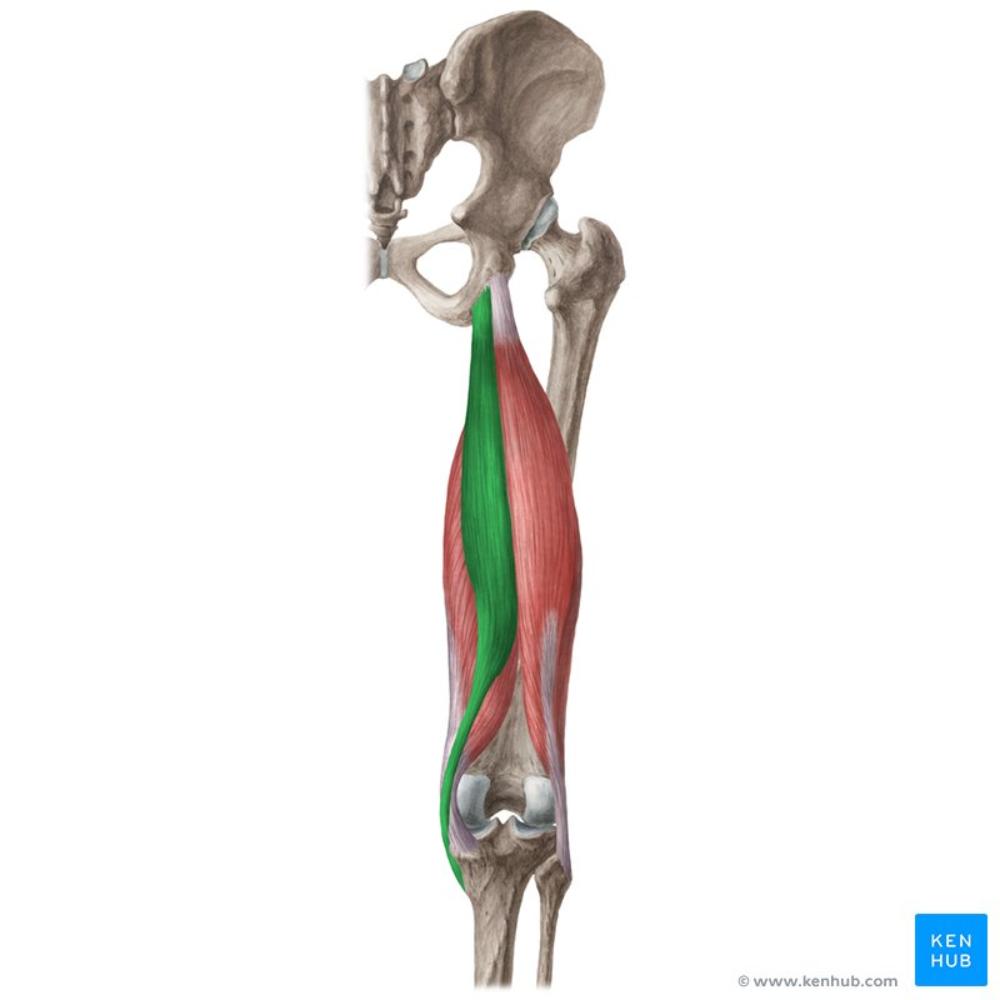

sartorius

O: ASIS

I: upper part of medial surface of shaft of tibia

A: Flexes, abducts, external rotation of femur; slight internal

rotation of leg at the knee joint

after flexion

N: femoral nerve